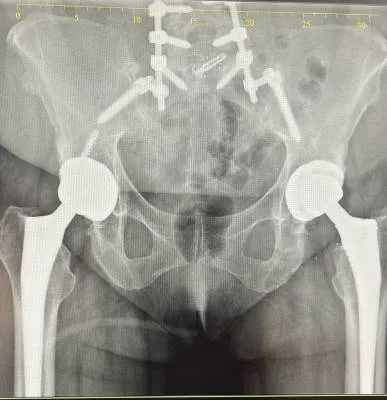

Dr. Haytham Elkhatib is a distinguished orthopaedic surgeon specializing in comprehensive musculoskeletal care. With expertise in trauma, fracture treatment, and advanced interventional joint injections, he offers innovative solutions for various conditions.

I had a Total hip replacement surgery with Dr. Haytham , and I am extremely happy with the result. I was able to walk on the same day of the operation, which was truly amazing. Now, one month after the surgery, I feel a great improvement. I have come back to life — I can walk every day after being unable to walk before, and I’ve regained all my muscle strength. Dr. Haytham’s team was incredibly professional and supportive; they didn’t leave me alone for a moment. I’m very thankful to Dr. Haitham and his wonderful team for their excellent care.